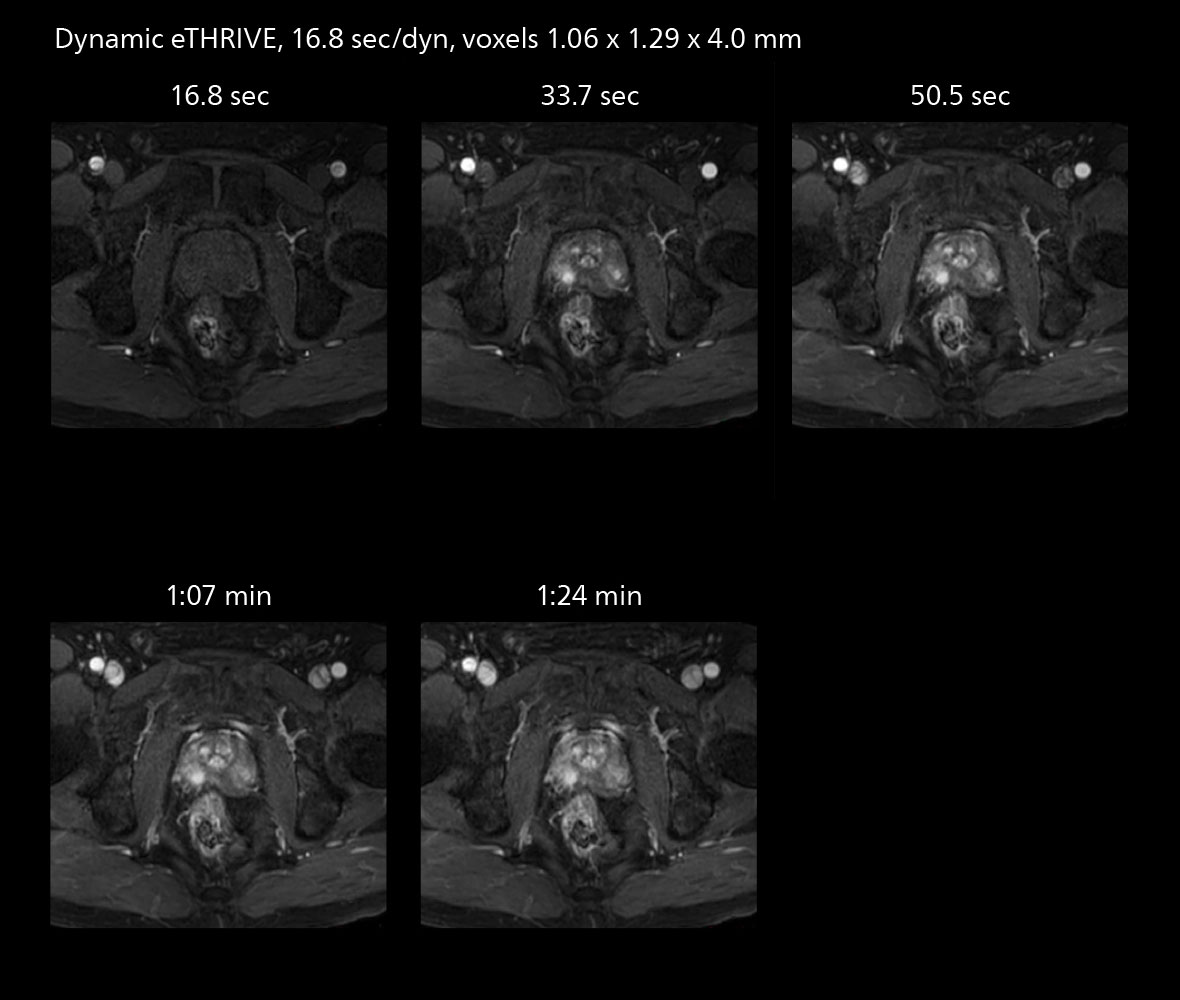

The high performance of the Vega HP gradients is particularly impressive in DWI. “The Vega HP gradients enable us to scan faster and use b-values as high as 2000, for example in prostate DWI and in DWIBS, which provides image quality that is remarkably improved over the previous system and we are able to more easily see lesions.”

MRI of prostate

Examples of prostate imaging showing faster scan times and improved resolution illustrate the power of SmartPath to Elition X in this case of prostate cancer with PI-RADS score 4.